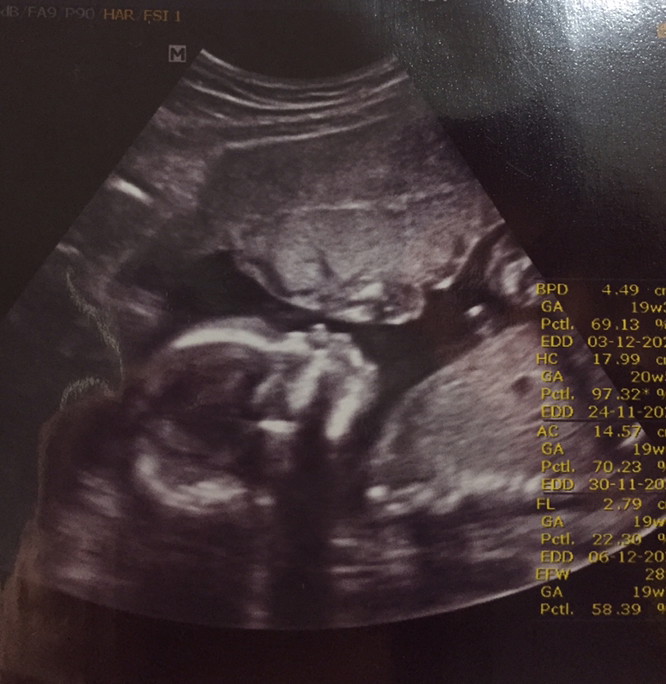

19week ได้ลูกชาย